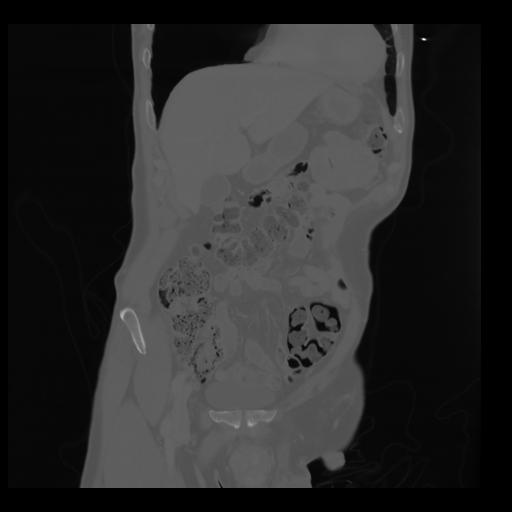

35 CUERPO,CE,Coronal,3.000,CUERPO,Coronal,